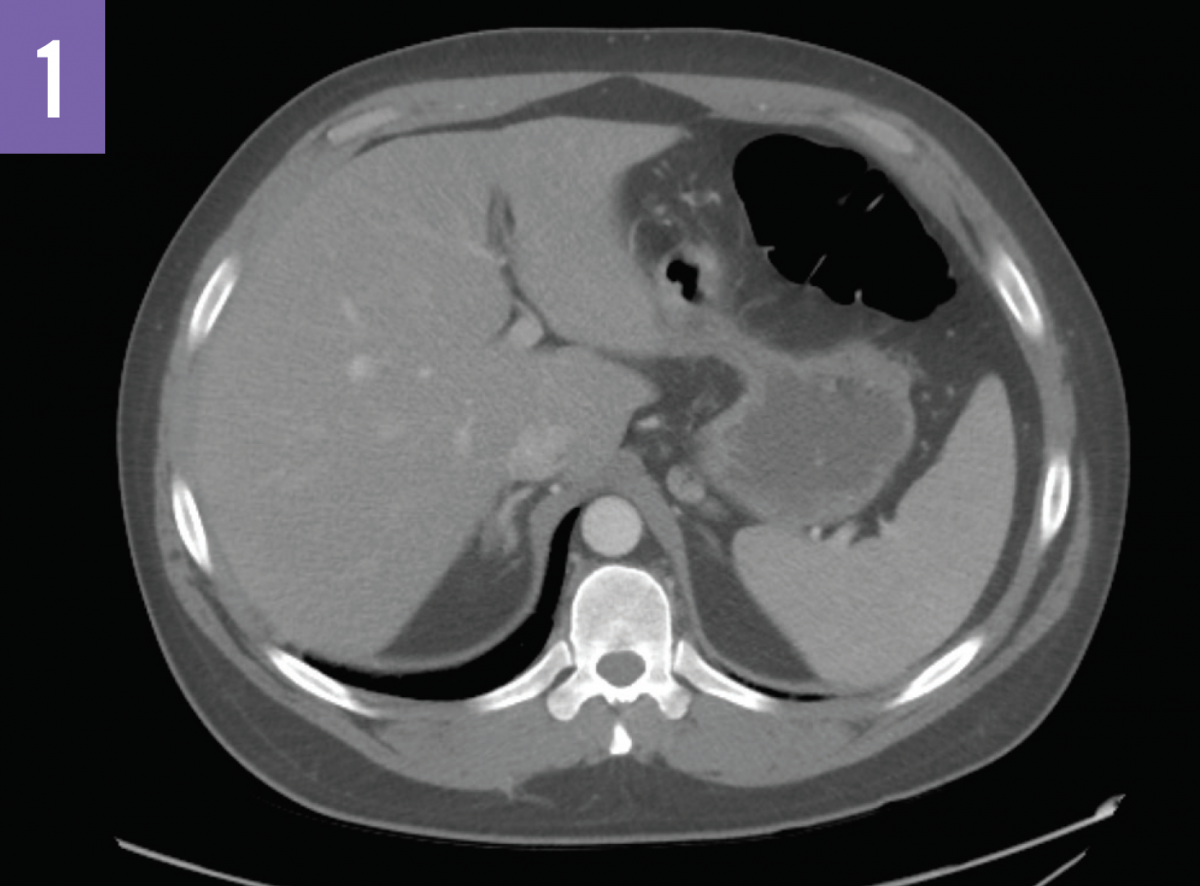

Computed tomography (CT) scans of the abdomen (Figures 1 and 2) showed acute bilateral adrenal gland enlargement. Compared with abdominal CT scans done 10 days prior for acute cholecystitis, these findings were new and highly suggestive of acute bilateral adrenal hemorrhage. His serum cortisol level was found to be <0.16 µg/dL (reference range, 5-25 µg/dL). The patient remained hemodynamically stable. Results of repeated laboratory tests for APLS, including anticardiolipin antibody and lupus anticoagulant testing, were positive for APLS.